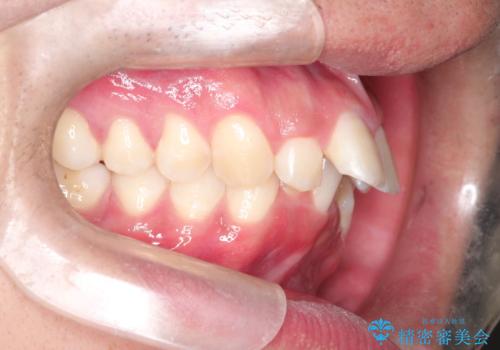

インビザラインによる出っ歯の矯正

- 出っ歯と下の歯のガタガタを主訴に来院されました。

上の奥歯を後方に移動させて、スペースを作り前歯を内側に引っ込める計画としました。

インビザラインによるマウスピース矯正で治療をすることとしました。